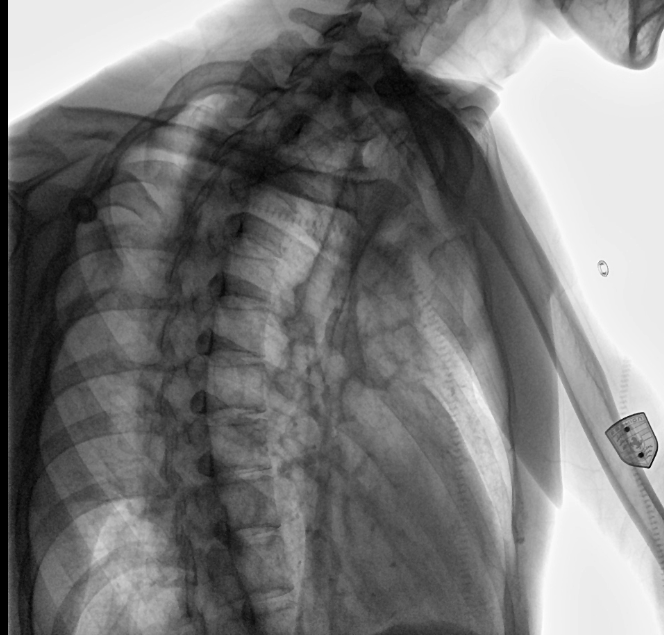

位于衡水市中醫(yī)醫(yī)院的動態(tài)平板數(shù)字化X射線系統(tǒng)DTP571具備高速高清點片功能。這是一款對放射科十分友好的產(chǎn)品。因為它把高速和高清點片結(jié)合,既能方便影像技師有效地抓拍需要的病灶的影像,又能給予影像醫(yī)生清晰的影像進行診斷

動態(tài)觀察診斷,實時高清點片